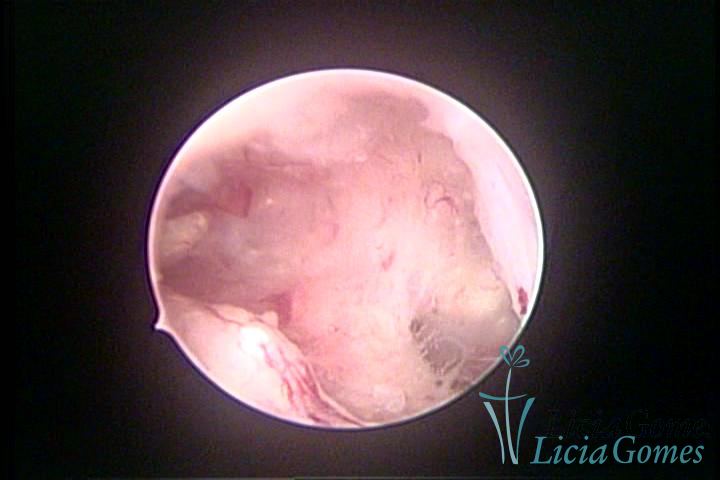

Este pode apresentar uma gama variável de aspectos macroscópicos, com aspecto pseudopolipoide; lembrando tecido cerebroide ou com reação deciduoide;a vascularização superficial é mais evidente e com vasos em formatos de saca-rolha ou espirais visualizando também a vascularização com atípias, com aumento do calibre dos vasos superficiais, pode ser encontrado também tecido em necrose, poderá haver um pequenos dendritos (papilomatoso).